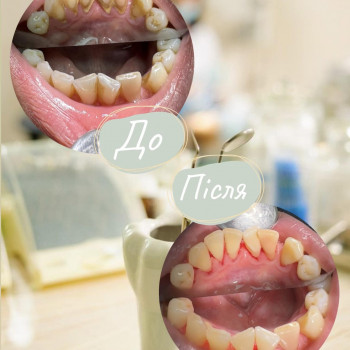

- Хочу рекомендувати дану стоматологію. Звернувся з болем у зубі. Лікування карієсу пройшло швидко та якісно. Рекомендую......

- Приходится периодически посещать Olis Dent, хорошо что стоматология находится не далеко. В общем 4 раза за два года была и всё для того чтобы зубы запломбировать.......

- Пока только два раза была в Goncharenko Dental Clinic. Оба раза пломбы на зубах мне ставили, на разные зубы кстати. Мне стоматология нравится. Она......